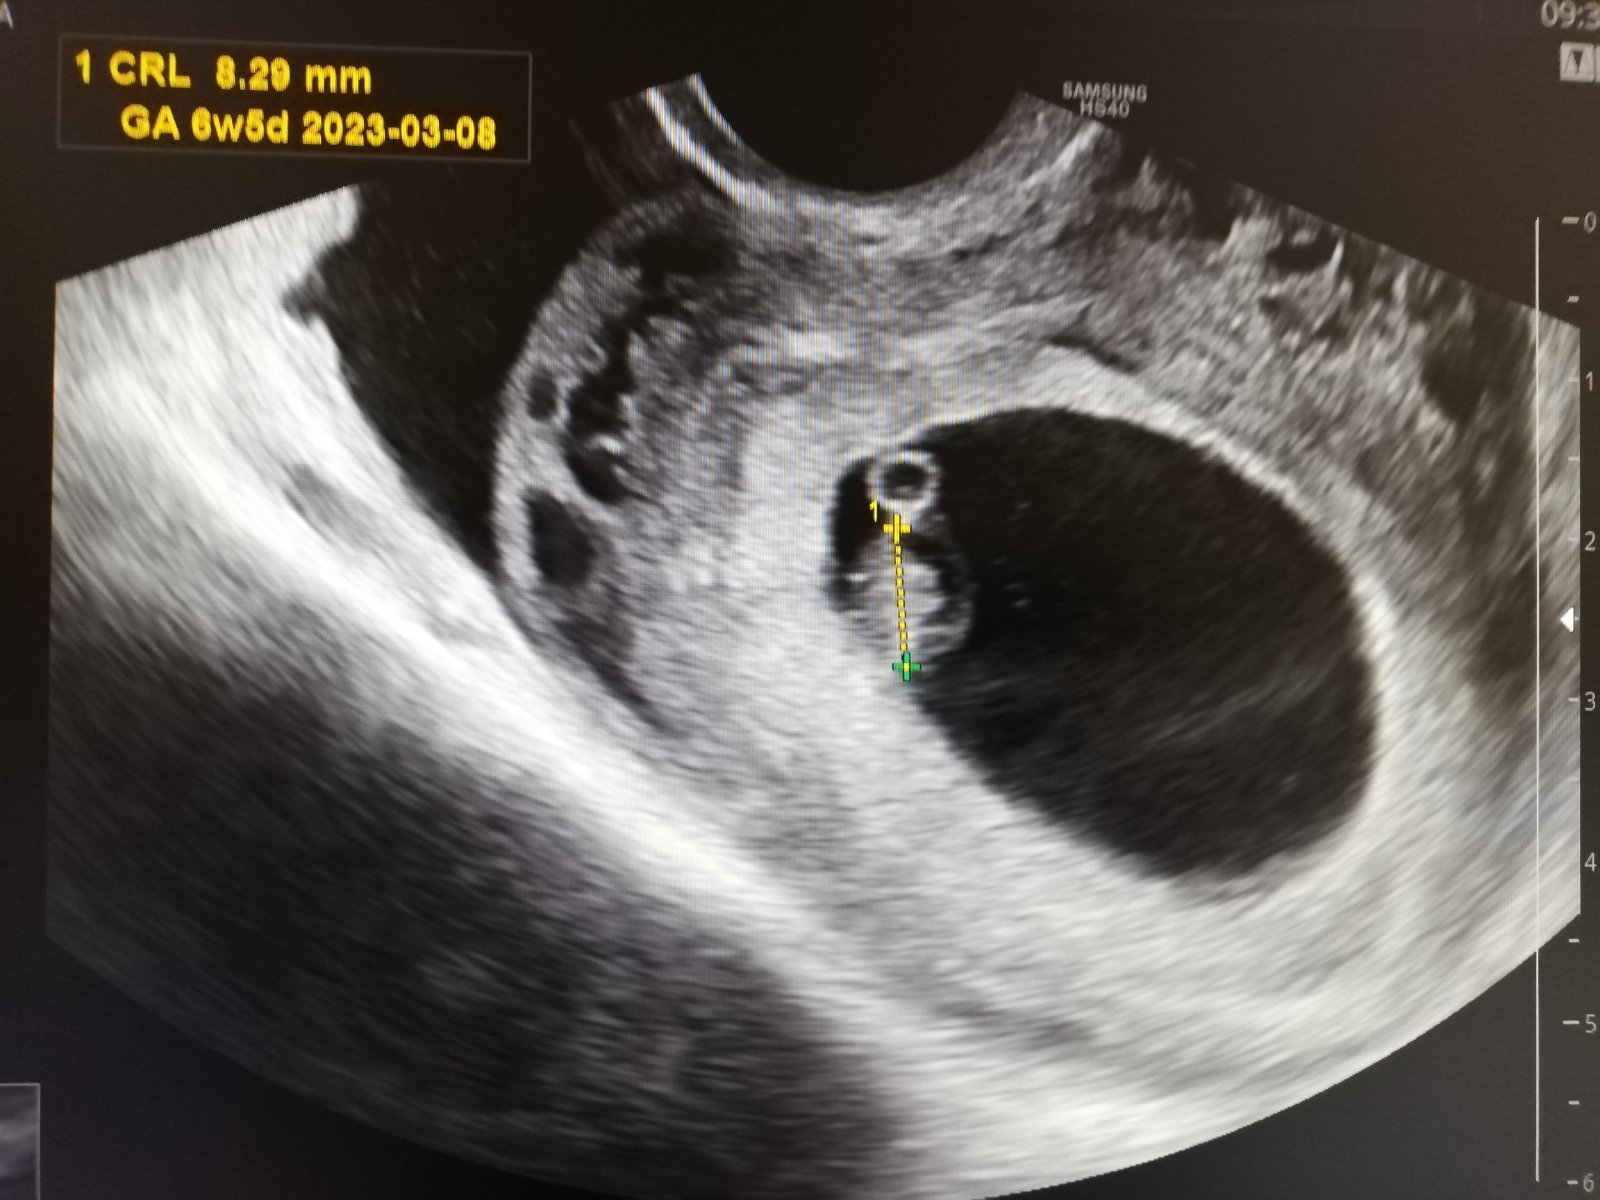

Tak holky.. Srdíčko je tam❤️❤️❤️. Já se tak bála a ono je tam!

@renat23 termín mi dal 8.3. Ale u každého těhu mi dal termín o týden pozdější a pak se to srovnalo, takže těch 4.3 bude odpovídat. Dneska podle něj 6+5 a má 8mm. Na kontrolu jdu až 23.8, těsně před screeningem. Zdá se mi to jako šíleně vzdálená doba. Ale zítra si ještě skočím nakrev kvůli štítné žláze.